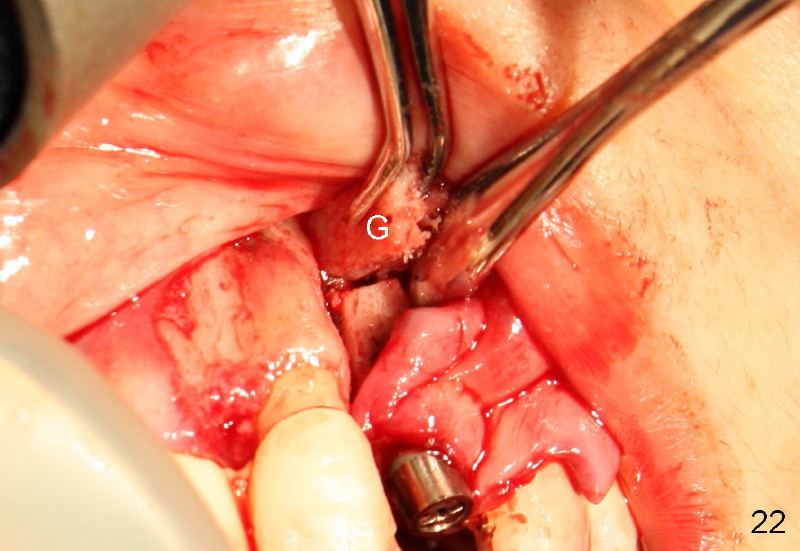

Segmental Osteotomy for Misplaced Implant

This corrective surgery was performed by Dr. Bernee Dunson.

Xin Wei, DDS, PhD, MS 1st edition 12/21/2011, last revision 12/23/2011